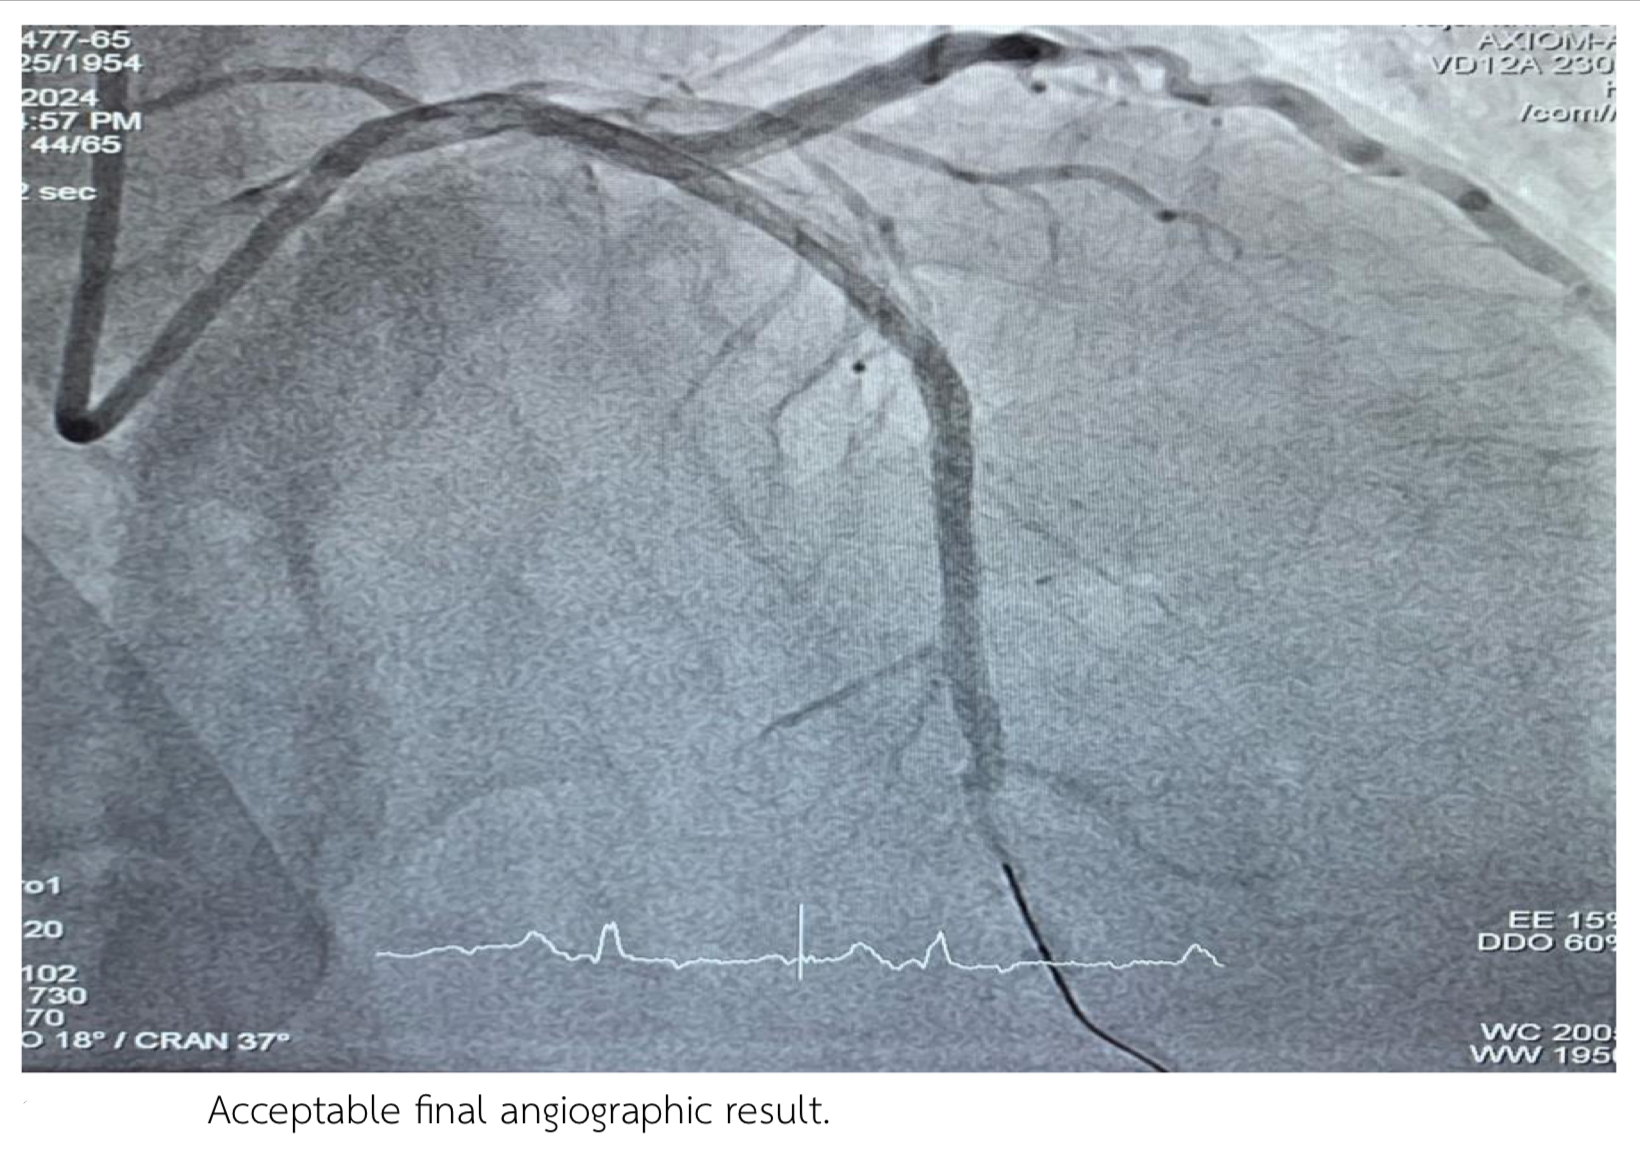

Staged PCI to CTO LAD:Access right distal radial access (DRA) in the anatomical snuffbox.Guiding Catheter: 5 Fr Ikari guiding catheterSion with finecross pass to LAD then change to Fielder XT pass through CTO LAD.Tip injection revealed true lumen wiring .Semi-compliant balloon 2.0 x 15 mm inflated p-dLAD upto 14 atm.Xience ProA 2.5 x 38 mm deployed mid to distal LAD upto 12 atm. Resolute integrity 2.75 x 30 mm deployed proximal to mid LAD upto 12 atm. Acceptable angiographic result.